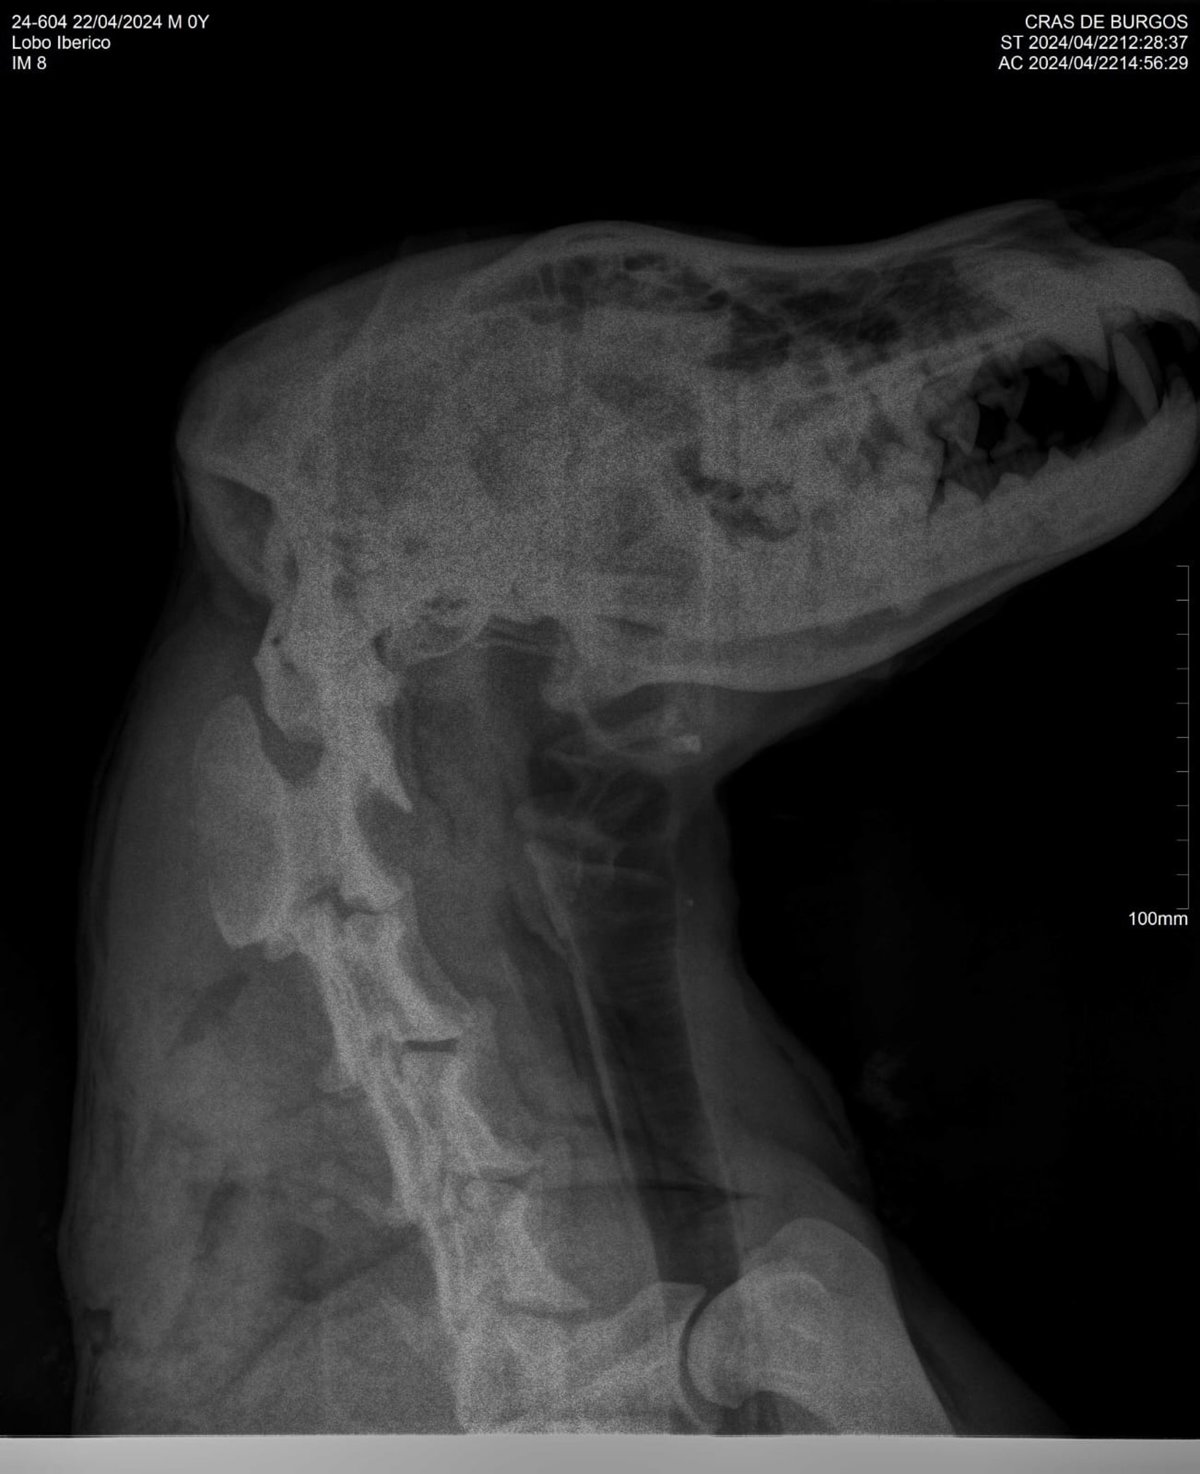

Radiografía del lobo.

Radiografía del lobo. - JCYL